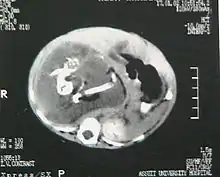

Fetus in fetu may be a parasitic twin fetus growing within its host twin. Very early in a monozygotic twin pregnancy, in which both fetuses share a common placenta, one fetus wraps around and envelops the other. The enveloped twin becomes a parasite, in that its survival depends on the survival of the host twin, by drawing on the host twin's blood supply. The parasitic twin is anencephalic (without a brain) and lacks some internal organs, and as such is unable to survive on its own. As the host twin has to "feed" the enveloped twin from the nutrients received over a single umbilical cord, they usually die before birth.